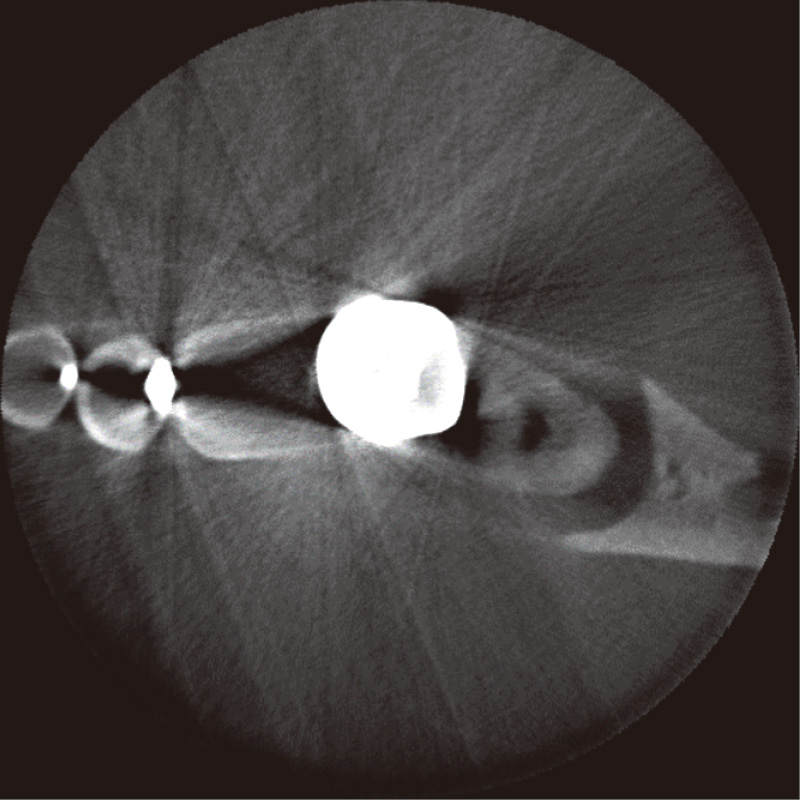

i-Dixelで図2の画像にMARを適用すると、図3の画像を得る。MAR前には、金属冠や金属修復物(特に白い領域)から、白や黒の放射状の線が多数みられる。また、金属と金属の間には黒いバンドがみられる(厳密に言えばすべてが純粋な金属アーチファクトではないが、本稿ではこれらを金属アーチファクトと定義する)。i-DixelでMARを行い画像の構成を行うと、画像左上に黄色で「MAR」と表示される。本症例には、診断的な意味合いはないが、上述の放射状の線や黒い金属アーチファクトも低減される。